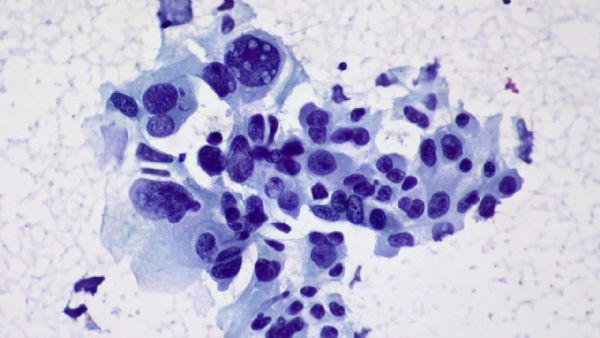

理论上讲,进入到肿瘤里面的杀伤性T细胞应该是为了杀灭癌细胞而生的。但是,Newell的团队却发现,患者肿瘤组织里面不仅有杀灭癌细胞杀伤性T细胞;还有大量与癌症无关的、原本应该是识别病毒的“旁观者”杀伤性T细胞,这些T细胞根本就“不认识”癌细胞。

跟癌症相关的杀伤性T细胞被癌细胞干趴下了,周围是一群没有抗癌能力的旁观者杀伤性T细胞

尤其是在那些预后差的癌症患者肿瘤组织中,旁观者杀伤性T细胞占比更多。这些旁观者杀伤性T细胞眼看着有杀癌细胞能力的T细胞被肿瘤组织耗竭,不会伸以援手,所以免疫检查点抑制剂拿这帮T细胞也是没办法了。